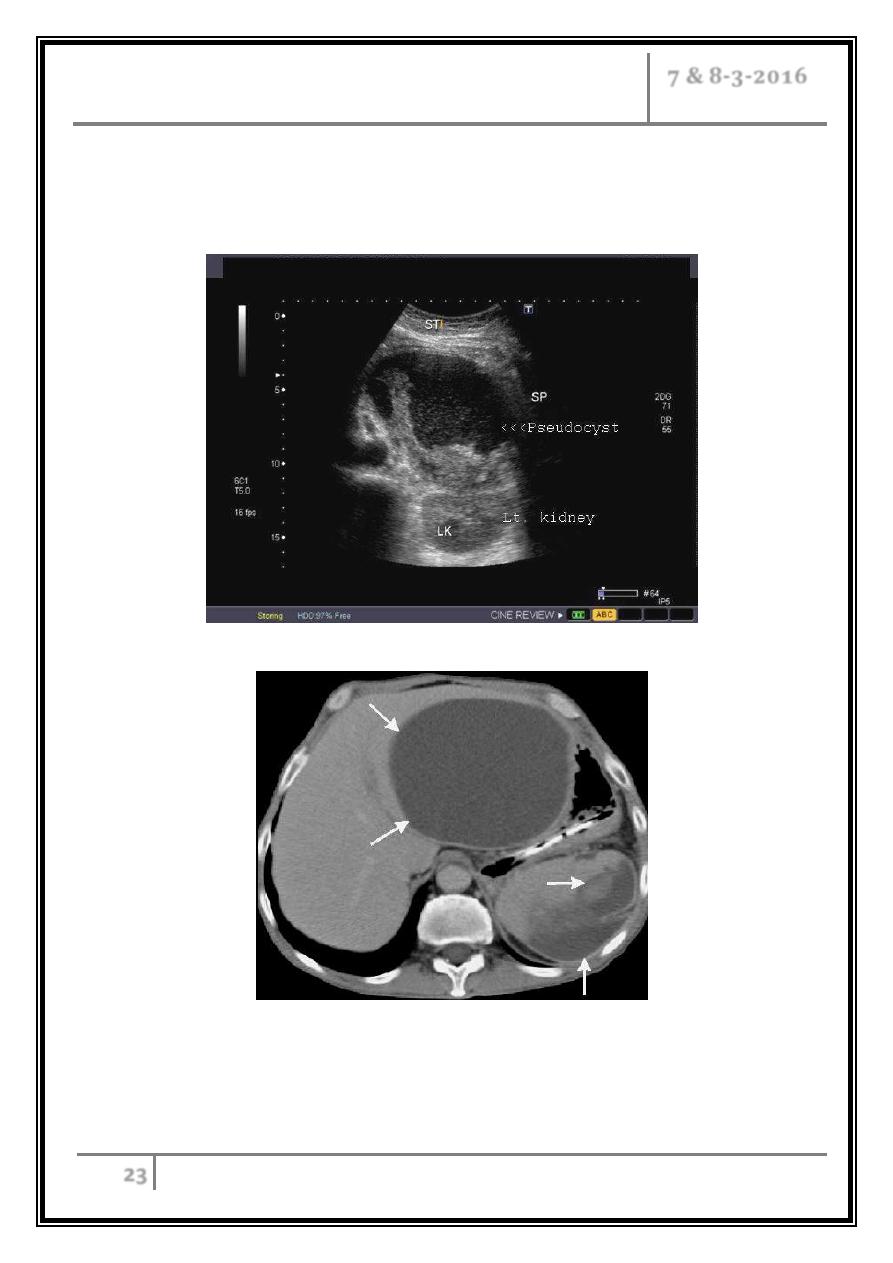

Pseudocysts and pancreatic ascites, which occur in both acute and chronic

Pancreatic pseudocyst

It’s the most common structural complication of chronic pancreatitis.

It’s a fluid collection surrounded by granulation tissue.

Intra- or retroperitoneal rupture, bleeding or cyst infection occurs.

The larger cysts may occlude nearby structures including the duodenum and the

bile duct.

In pseudocysts, less than 6 cm in diameter, spontaneous resolution can be

anticipated.

In larger cysts that have been present for a period in excess of 6 weeks,

resolution is uncommon and a long-term complication rate of approximately

30% can be anticipated.

Many pseudocysts are closely opposed to the posterior wall of the stomach or

duodenum and can be successfully drained endoscopically using endoscopic

ultrasound to identify the optimum drainage site. A direct fistula is created

between the pseudocyst lumen and the gastric or duodenal lumen which is then

kept patent by the insertion of plastic stents. This approach will be successful in

approximately 75% of cases.

Pancreatic pseudocyst

CT examination: A giant, sharp-contoured, hypodense lesion is depicted

(arrows). Is pancreatic pseudocyst in the omental bursa